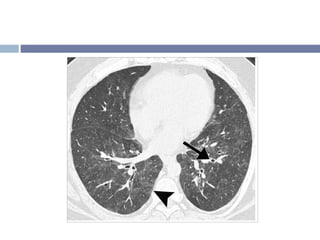

TCAR Áreas irregulares de consolidación de bordes mal definidos (80%) Opacidades en vidrio despulido de distribución irregular (60%) o perilobular Broncograma aéreo en las áreas de consolidación

Distribución Generalmente bilateral, en parches Periférico, subpleural Principalmente basal El volumen pulmonar es normal

Otros signos radiológicos Nódulos centrilobulares (50%) Opacidades lineales irregulares 1 o más nódulos mayores de 3 cm (Opacidades grandes redondeadas) DP moderado